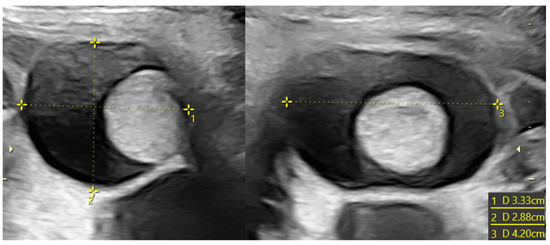

Figure 4. Ovarian cyst with hemorrhagic content in a female fetus at 33 weeks of pregnancy (3.5 cm of diameter). The formation did not regress, and a laparoscopic cystectomy was performed; at the histological examination, necrosis was reported.